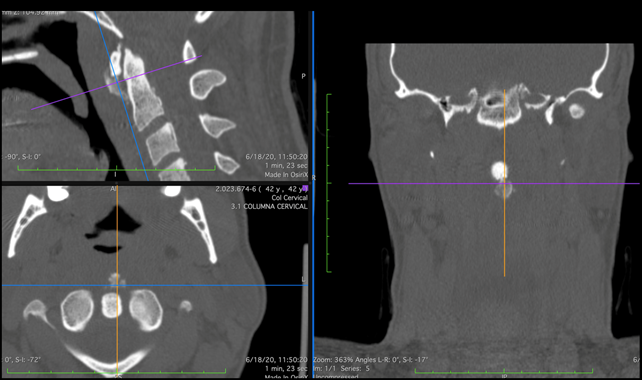

Se solicitó TAC urgente que identificó un aumento del espacio prevertebral, con la presencia de gran calcificación que se extendía anteriormente desde sector inferior al arco del Atlas hasta la base de la apófisis odontoides; orientando al diagnóstico de tendinitis calcificante del músculo largo del cuello. Se realiza además de forma urgente RNM de cuello, donde se evidencia extensa imagen hiperintensa retrofaríngea en relación directa con calcificación antes descripta, llegando hasta sector anterior nivel de C5.

Figura 3: TAC de nuestro caso problema, cortes sagital, coronal y axial, donde se observa la calcificación que se extiende desde el sector inferior del arco anterior del Atlas hacia el sector anterior de la base de la apófisis odontoides.